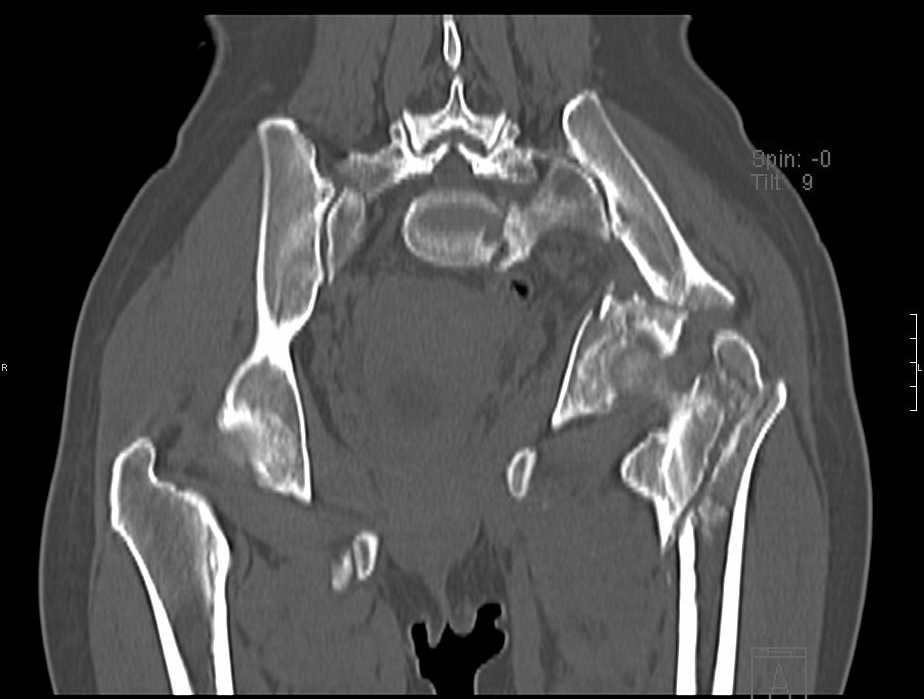

Перелом свода и основания черепа. Вертикально-нестабильное повреждение таза, осложнённое разрывом мочевого пузыря. Чрезвертельный перелом левого бедра. Перелом правой таранной кости, переломовывих правой кубовидной кости. Тупая травма живота, разрыв печени, ушиб почек. Забрюшинная гематома. В день травмы - лапаротомия, ушивание ран печени. Разрыв мочевого пузыря не диагностирован. Течение болезни осложнилось развитием мочевого затёка и обширной пред- и забрюшинной флегмоны, сформировался свищ мочевого пузыря. 19.8.2008 вскрытие, дренировние флегмоны, ревизия мочевого пузыря, обтурация мочевого свища (свищ закрылся в октябре), 1.10.2008 некрэктомия, пластика по Шеде-Лидскому правой кубовидной кости. По результатам КТ диагностирован рак правой почки (диагностическая находка), 8.10.2008 нефрэктомия справа.

Имеется вертикальное смещение левой половины таза с выраженным отведением крыла (клинически подвижности нет), несросшийся низкий двухколонный перелом левой вертлужной впадины с потерей конгруэнтности, укорочение около5 см, застарелый разрыв лонного сочленения, неправильно сросшиеся переломы обеих ветвей правой лонной кости с укорочением, патологическая подвижность лоно-седалищного фрагмента слева. Правая нижняя конечность неопорна, несмотря на то, что лежа прямую ногу поднимает, ходит на левой ноге (ортопедическая обувь) с костылями, справа тазобедренный ортез. Седалищные нервы работают. Урологи отпустили больную на 6 мес.